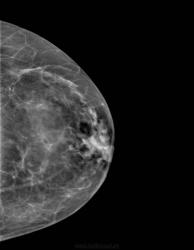

Возможности "цветовой" обработки цифрового изображения молочной железы.